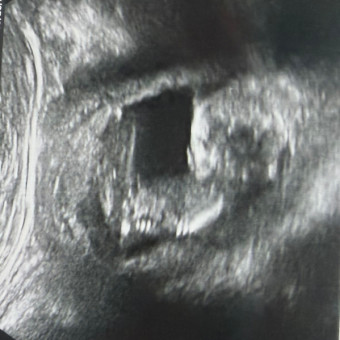

September 30, 2026

Thank you for checking out our registry and being willing to contribute to the arrival of our baby boy. We appreciate your support more than you know. If you have questions, do not hesitate to reach out. Love, Ivanna, Nick & Louie